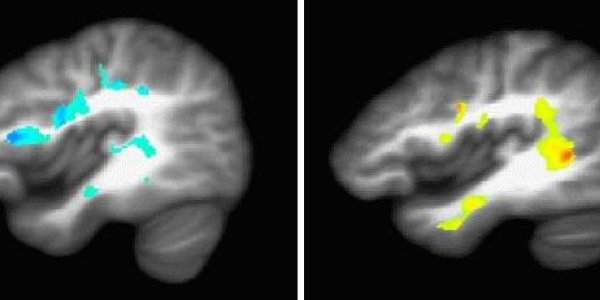

Recent studies have suggested that autism spectrum disorder (ASD) may be more prevalent among children born very prematurely. The early symptoms of ASD are also associated with other conditions…